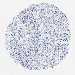

CANCER BREAST CANCER Show tissue menu

BRCA TCGA BRCA VALIDATION PROTEIN EXPRESSION